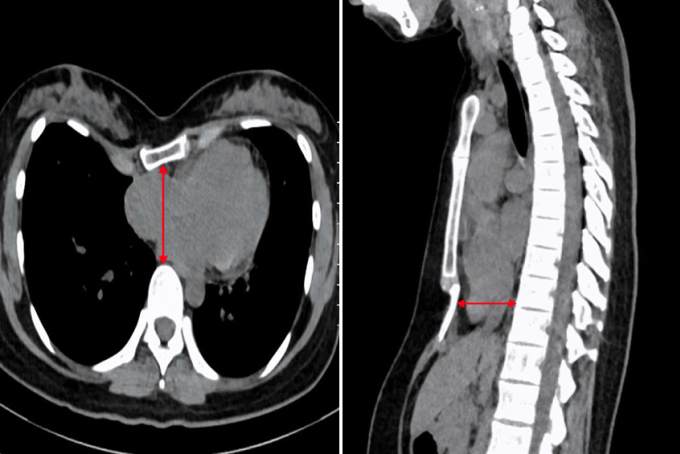

ThS.BS.CKI Phạm Ngọc Minh Thủy, khoa Ngoại Tim mạch, Trung tâm Tim mạch, Bệnh viện Đa khoa Tâm Anh TP HCM, cho biết chị Tây bị lõm ngực nặng, lệch về bên phải. Kết quả chụp cắt lớp vi tính ghi nhận chỉ số Haller là 5,2 (tỷ lệ giữa đường kính ngang và đường kính trước sau của ngực, bình thường chỉ số này dưới 2,5).